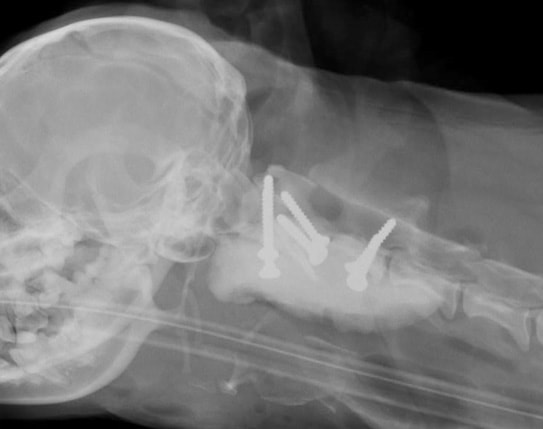

環椎軸椎不安定症の犬を外科的に整復を行った症例

|  環椎と軸椎を固定するスクリューを2本挿入します。 |

|  次に環椎に2本、軸椎に2本のスクリューを挿入します。 |

|  環椎軸椎関節軟骨に上腕骨から採取した海綿骨移植を行います。 |

|  最後に外科用ボーンセメントで固定して終了です。 |

|  手術後のレントゲン写真 |